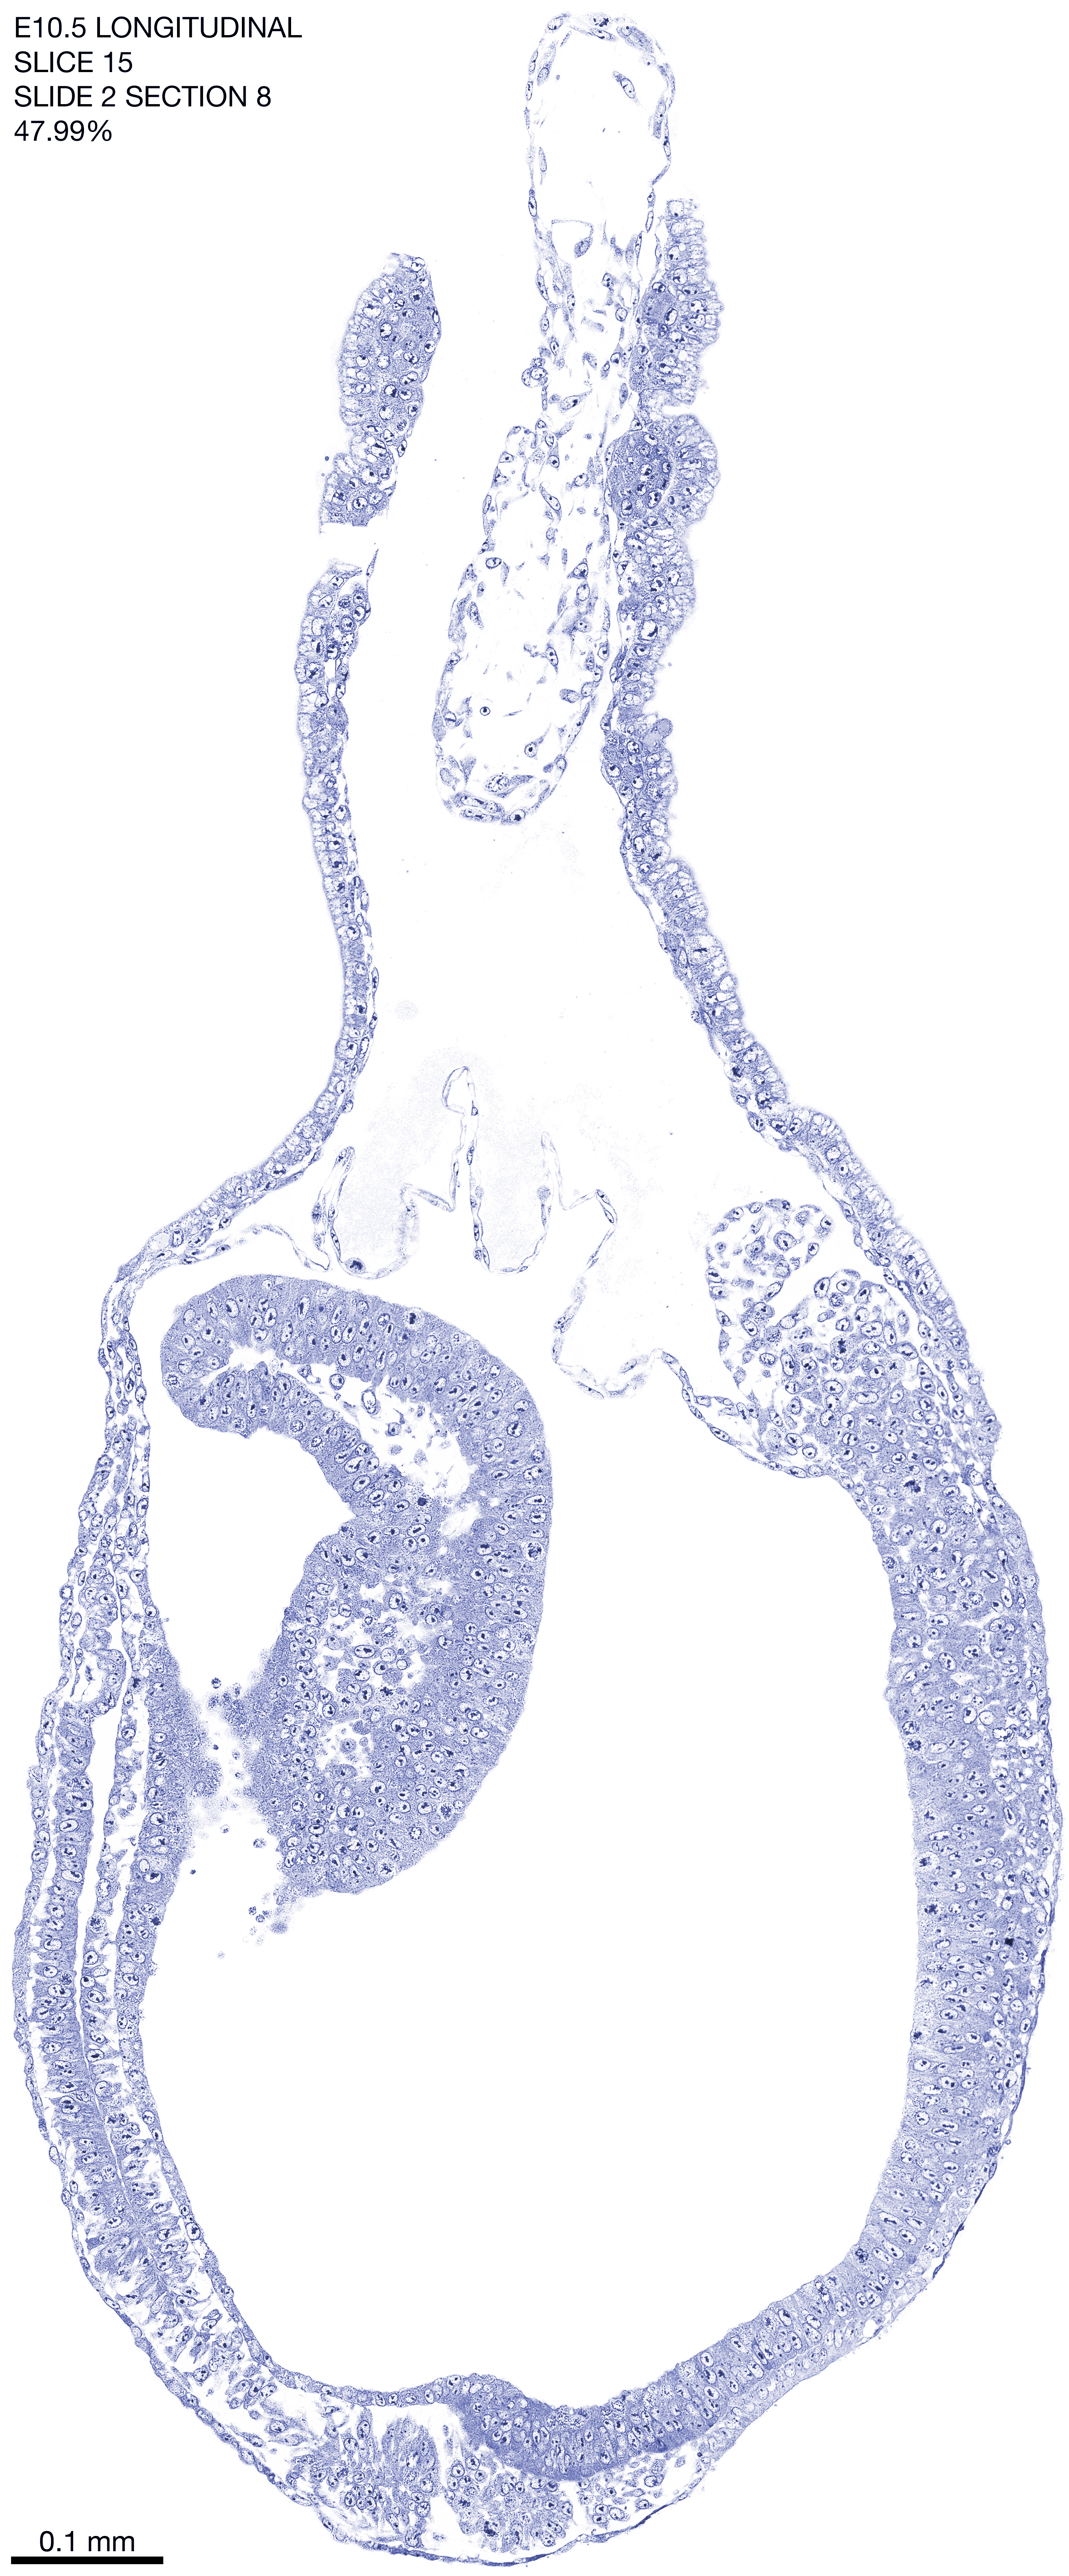

E10.5 Longitudianal Archive This page contains jpg files of ALL SLICES (each 3µm thick) that were scanned of the E10.5 longitudinally cut specimen. Download: Large | High Res Download: Large | High Res Download: Large | High Res Download: Large | High Res Download: Large | High Res Download: Large | High Res Download: Large | High Res Download: Large | High Res Download: Large | High Res Download: Large | High Res Download: Large | High Res Download: Large | High Res Download: Large | High Res Download: Large | High Res Download: Large | High Res Download: Large | High Res Download: Large | High Res Download: Large | High Res Download: Large | High Res Download: Large | High Res Download: Large | High Res Download: Large | High Res Download: Large | High Res Download: Large | High Res Download: Large | High Res Download: Large | High Res Download: Large | High Res Download: Large | High Res Download: Large | High Res Download: Large | High Res Download: Large | High Res Download: Large | High Res Download: Large | High Res Download: Large | High Res Download: Large | High Res Download: Large | High Res Download: Large | High Res Download: Large | High Res Download: Large | High Res Download: Large | High Res Download: Large | High Res Download: Large | High Res Download: Large | High Res Download: Large | High Res Download: Large | High Res Download: Large | High Res Download: Large | High Res Download: Large | High Res Download: Large | High Res Download: Large | High Res Download: Large | High Res Download: Large | High Res Download: Large | High Res Download: Large | High Res Download: Large | High Res Download: Large | High Res Download: Large | High Res Download: Large | High Res